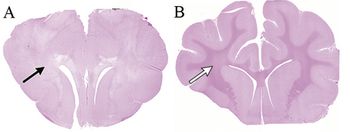

One Health team at UC Davis hopes to eventually cure this birth defect in canine and human patients.